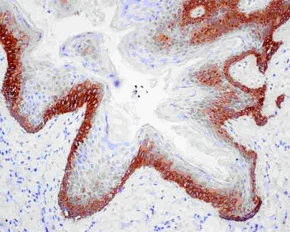

Immunohistochemistry (Formalin/PFA-fixed paraffin-embedded sections) - Anti-Cytokeratin 16/K16 antibody [EPR13504] - BSA and Azide free (AB240236)

Immunohistochemical analysis of paraffin-embedded Human skin tissue labeling Cytokeratin 16/K16 with ab181055 at 1/500 dilution followed by pre-diluted HRP-conjugated secondary antibody and counter-stained with Hematoxylin.

This data was developed using the same antibody clone in a different buffer formulation containing PBS, BSA, glycerol, and sodium azide (ab181055).

Perform heat mediated antigen retrieval with EDTA buffer pH 9 before commencing with IHC staining protocol.